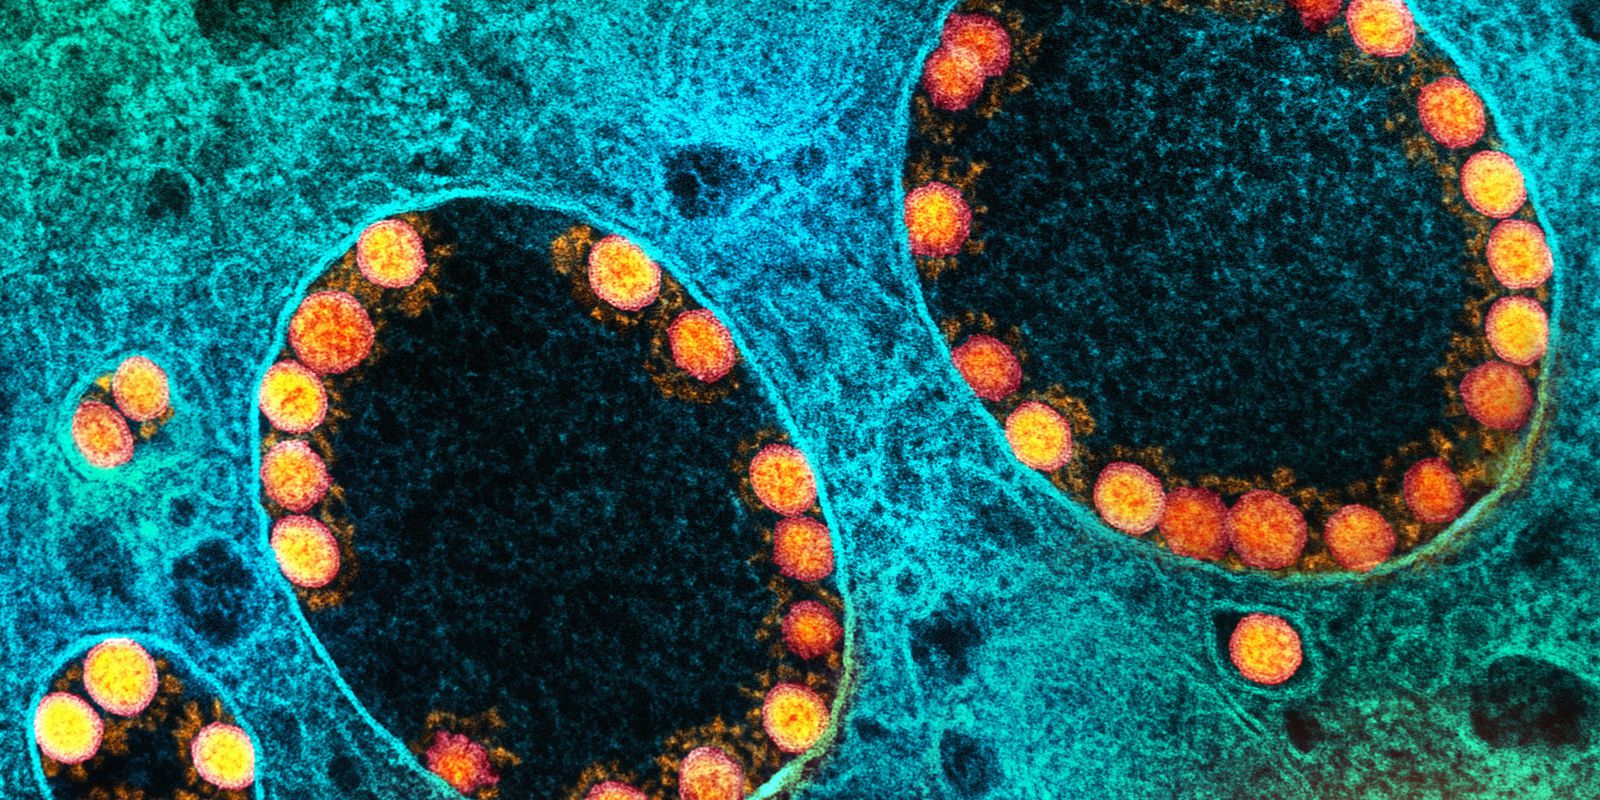

A meningite meningocócica é um tipo de meningite bacteriana causada pela bactéria Neisseria meningitidis, conhecida como meningococo. É uma doença que provoca uma inflamação nas meninges, membranas que envolvem o cérebro e a medula espinhal.

Seus principais sintomas são fraqueza, febre, dor de cabeça, vômitos e rigidez na nuca. Esses sintomas podem evoluir rapidamente, agravando o quadro do paciente e podendo causar até a morte, já nas primeiras 24 a 48 horas.